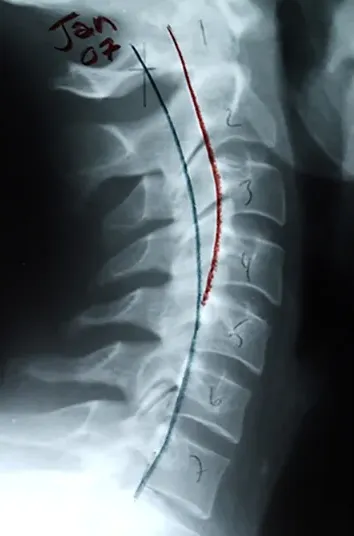

12 months later

There was a massive reduction in pain and symptoms during the first year of care! The curve in my neck started coming back, and neck and back pain was reduced by 90%. The left arm weakness and numbness were gone. The daily headaches ended! Weekly migraines were reduced to once a month. Sciatica in my right leg was gone. Life was returning!

In the 3rd year, my upper neck started moving and corrected more. Migraines stopped and my vision (convergence insufficiency) started improving.

What has been even more amazing to me, is that my spine has continued to improve every year for the past 18 years! Instead of deteriorating from phase 2 (visible degenerative disc and joint disease) at 30 years old, to phase 3 (advanced osteoarthritis) at over 54 years old, my spine is continuing to improve each year with chiropractic care!